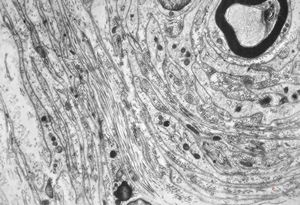

F,50y. | progressive multifocal leukoencephalopathy- viral particles in a glial cell